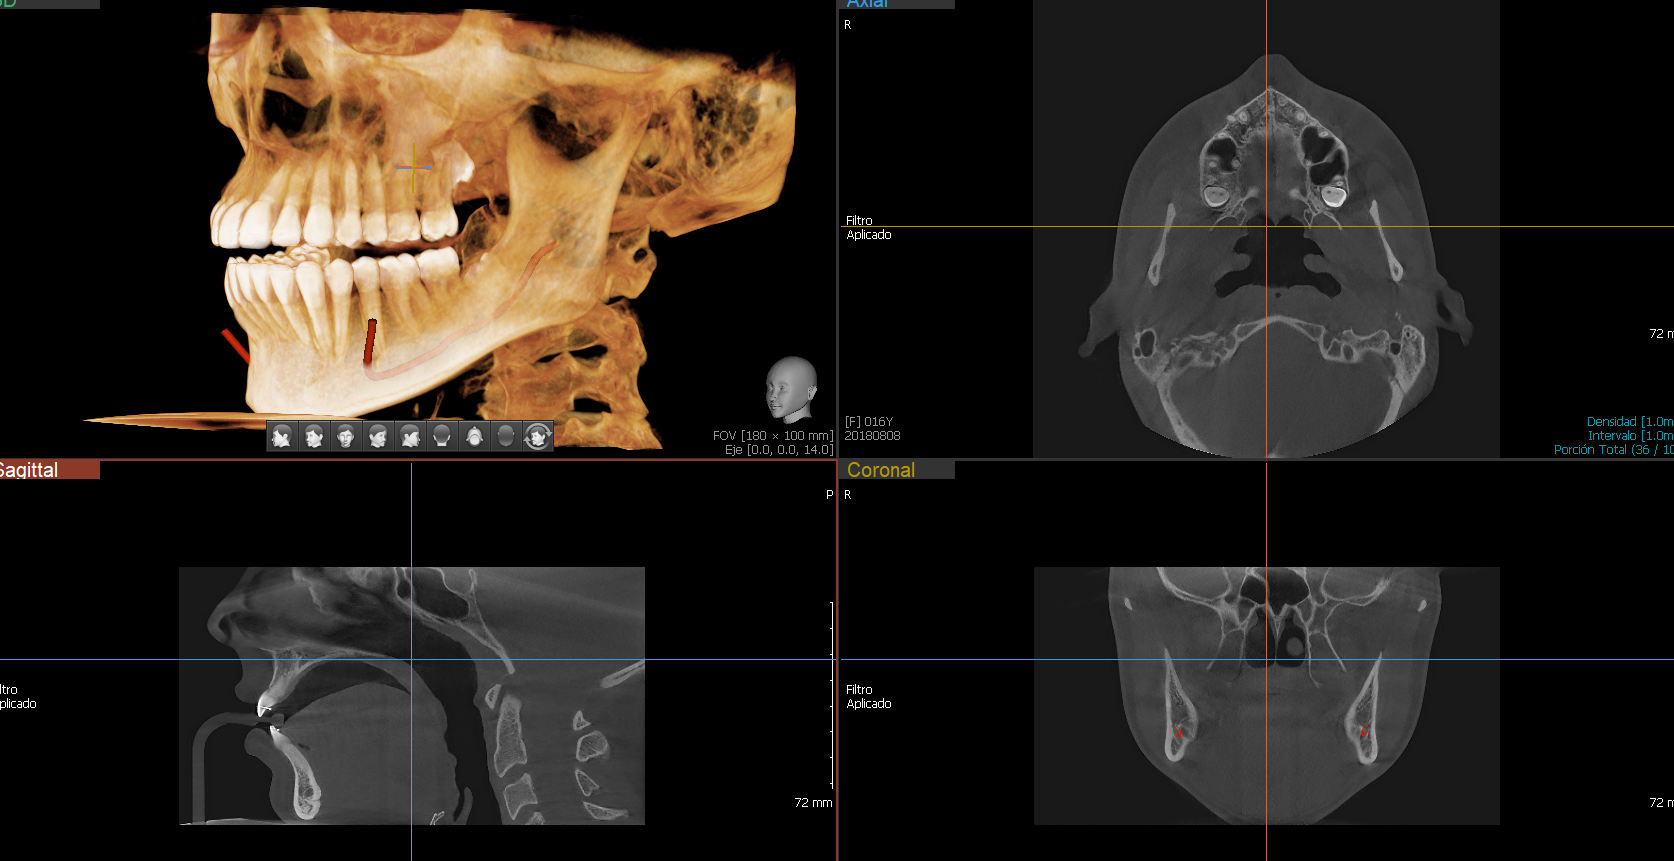

Green 16 es una avanzada proyección de imagen de rayos X digital 4-en-1, sistema que incorpora PANO, CEPH (opcional), CBCT y MODEL SCAN. Proporciona imágenes de alta calidad con menor radiación mediante la combinación de procesamiento de imágenes y acumuladas experiencias en imagen dental de VATECH. Esto mejorará su precisión de diagnóstico con un aumento de la planificación del tratamiento y la satisfacción del paciente.

Green 16/18 ofrece una gama de campos de visión seleccionables. Multi FOV permite al usuario seleccionar el modo FOV óptimo y minimizar la exposición a áreas que no son la región de interés. Seleccione el tamaño adecuado de FOV entre 16×9/18×10, 12×9/13×10, 8×9 y 5×5 basado en una particular necesidad de diagnóstico. Cubre la región del arco completo, seno y la ATM izquierda / derecha y es adecuado para la mayoría de los casos de cirugía oral así como la cirugía de implantes múltiples. También puede medir el volumen de la vía aérea.